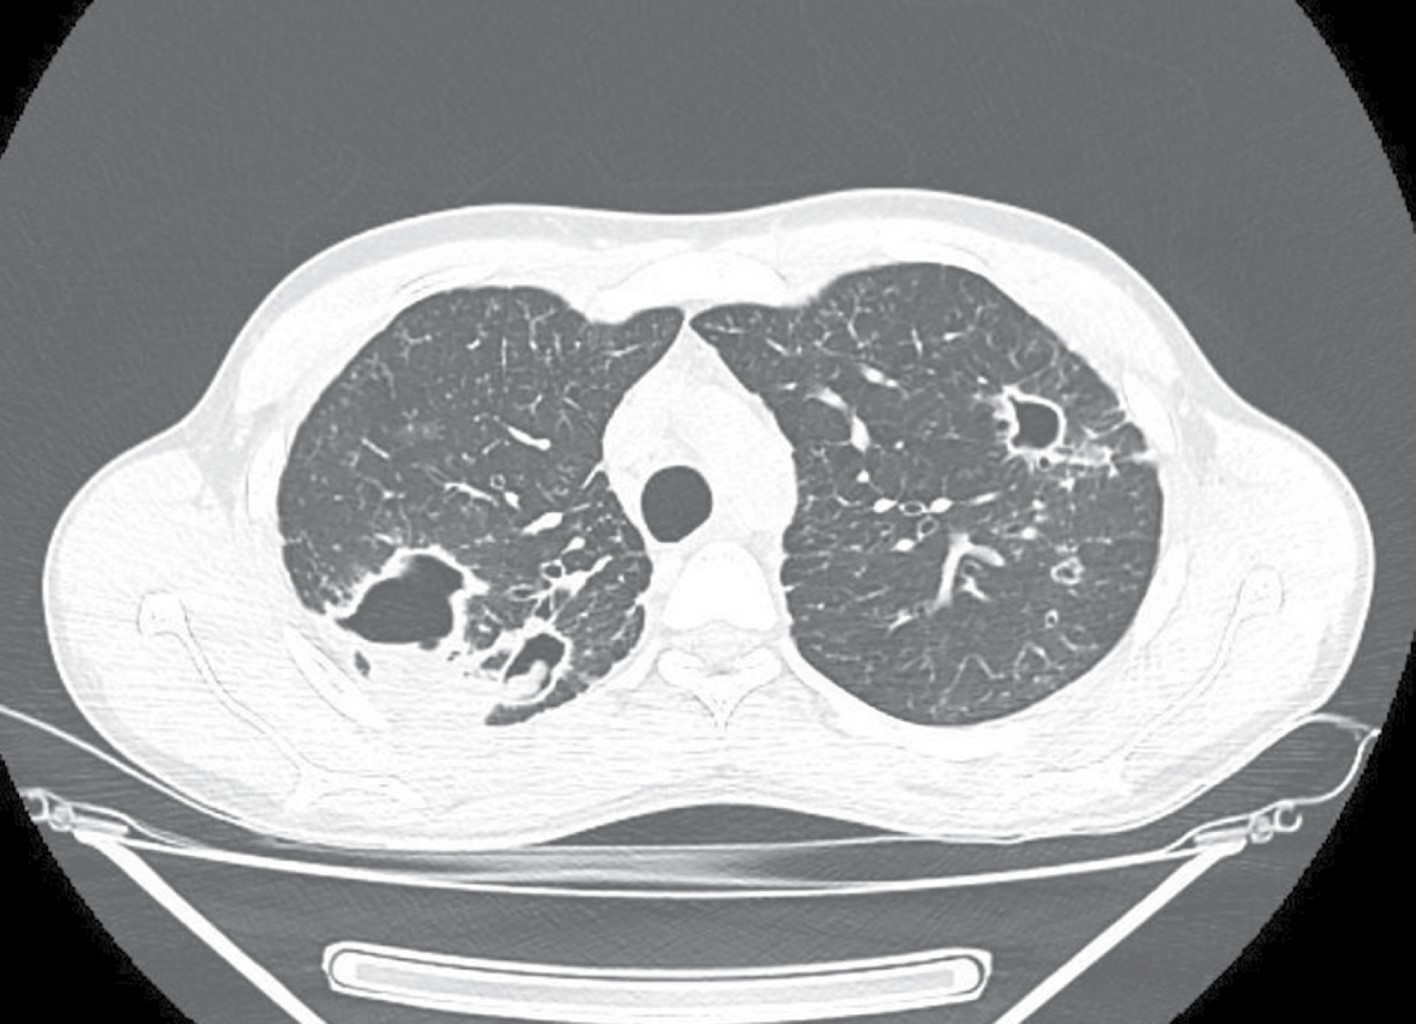

A 24-year-old male, originally from Sonora and residing in the city of Tijuana sought medical attention for his chronic respiratory symptoms. His clinical history was negative for substance abuse, and he did not report any significant illnesses in the past. Symptoms began a year earlier with cough and hemoptysis. He received private medical care, without a definitive diagnosis, and no information is available on the prescribed treatment. A chest CT showed fibrocavitary lesions in both upper pulmonary lobes, with an intracavitary mass suggestive of mycetoma (Figure 1). Given the suspicion of tuberculosis, a series of sputum smears were requested and later reported as negative, as well as an Xpert MTB/RIF (Mycobacterium tuberculosis complex not detected); as routinely done, a culture for mycobacteria was also processed. Sputum smears reported abundant spherules of Coccidioides spp.; later, a positive culture for Coccidioides spp. was reported, in addition to a positive coccidioidomycosis serology with an IgG titer of 1:64. No evidence of extrapulmonary involvement was detected during the clinical evaluation. Treatment with itraconazole 400 mg daily was started; after two months of treatment, the patient was asymptomatic and had gained 2.7 kg.

Clinical presentation can be similar, with prolonged constitutional symptoms, various respiratory syndromes, and chronic meningitis, years or decades after the initial exposure. Radiographic findings in the chest of patients with chronic pulmonary coccidioidomycosis are virtually identical to those of pulmonary tuberculosis, with the presence of cavitations and fibrous tracts.1